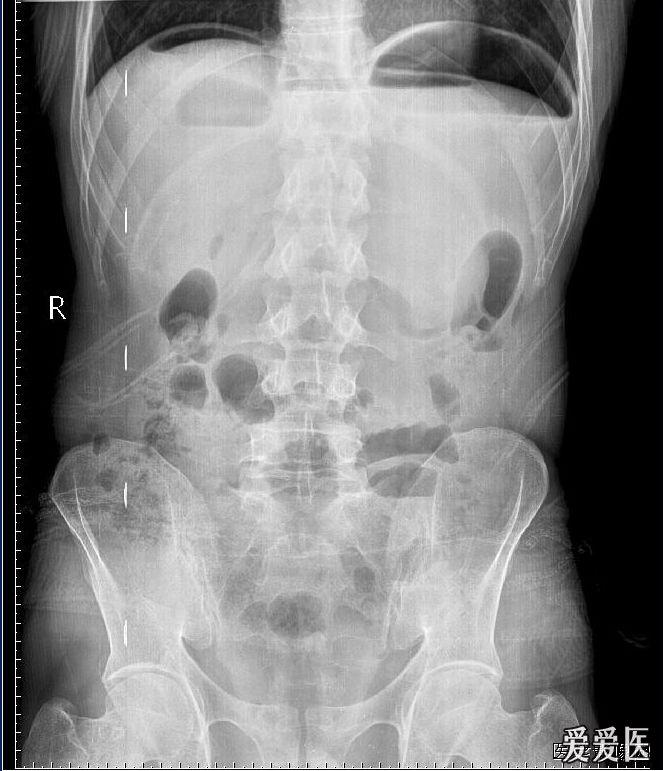

消化道穿孔影像图片

消化道穿孔影像图片,消化道穿孔图片

消化道穿孔,膈下间隙积液.jpg

消化道穿孔图片

消化道穿孔x线图片

消化道穿孔x片

消化道穿孔

消化道穿孔x线

消化道穿孔x线表现